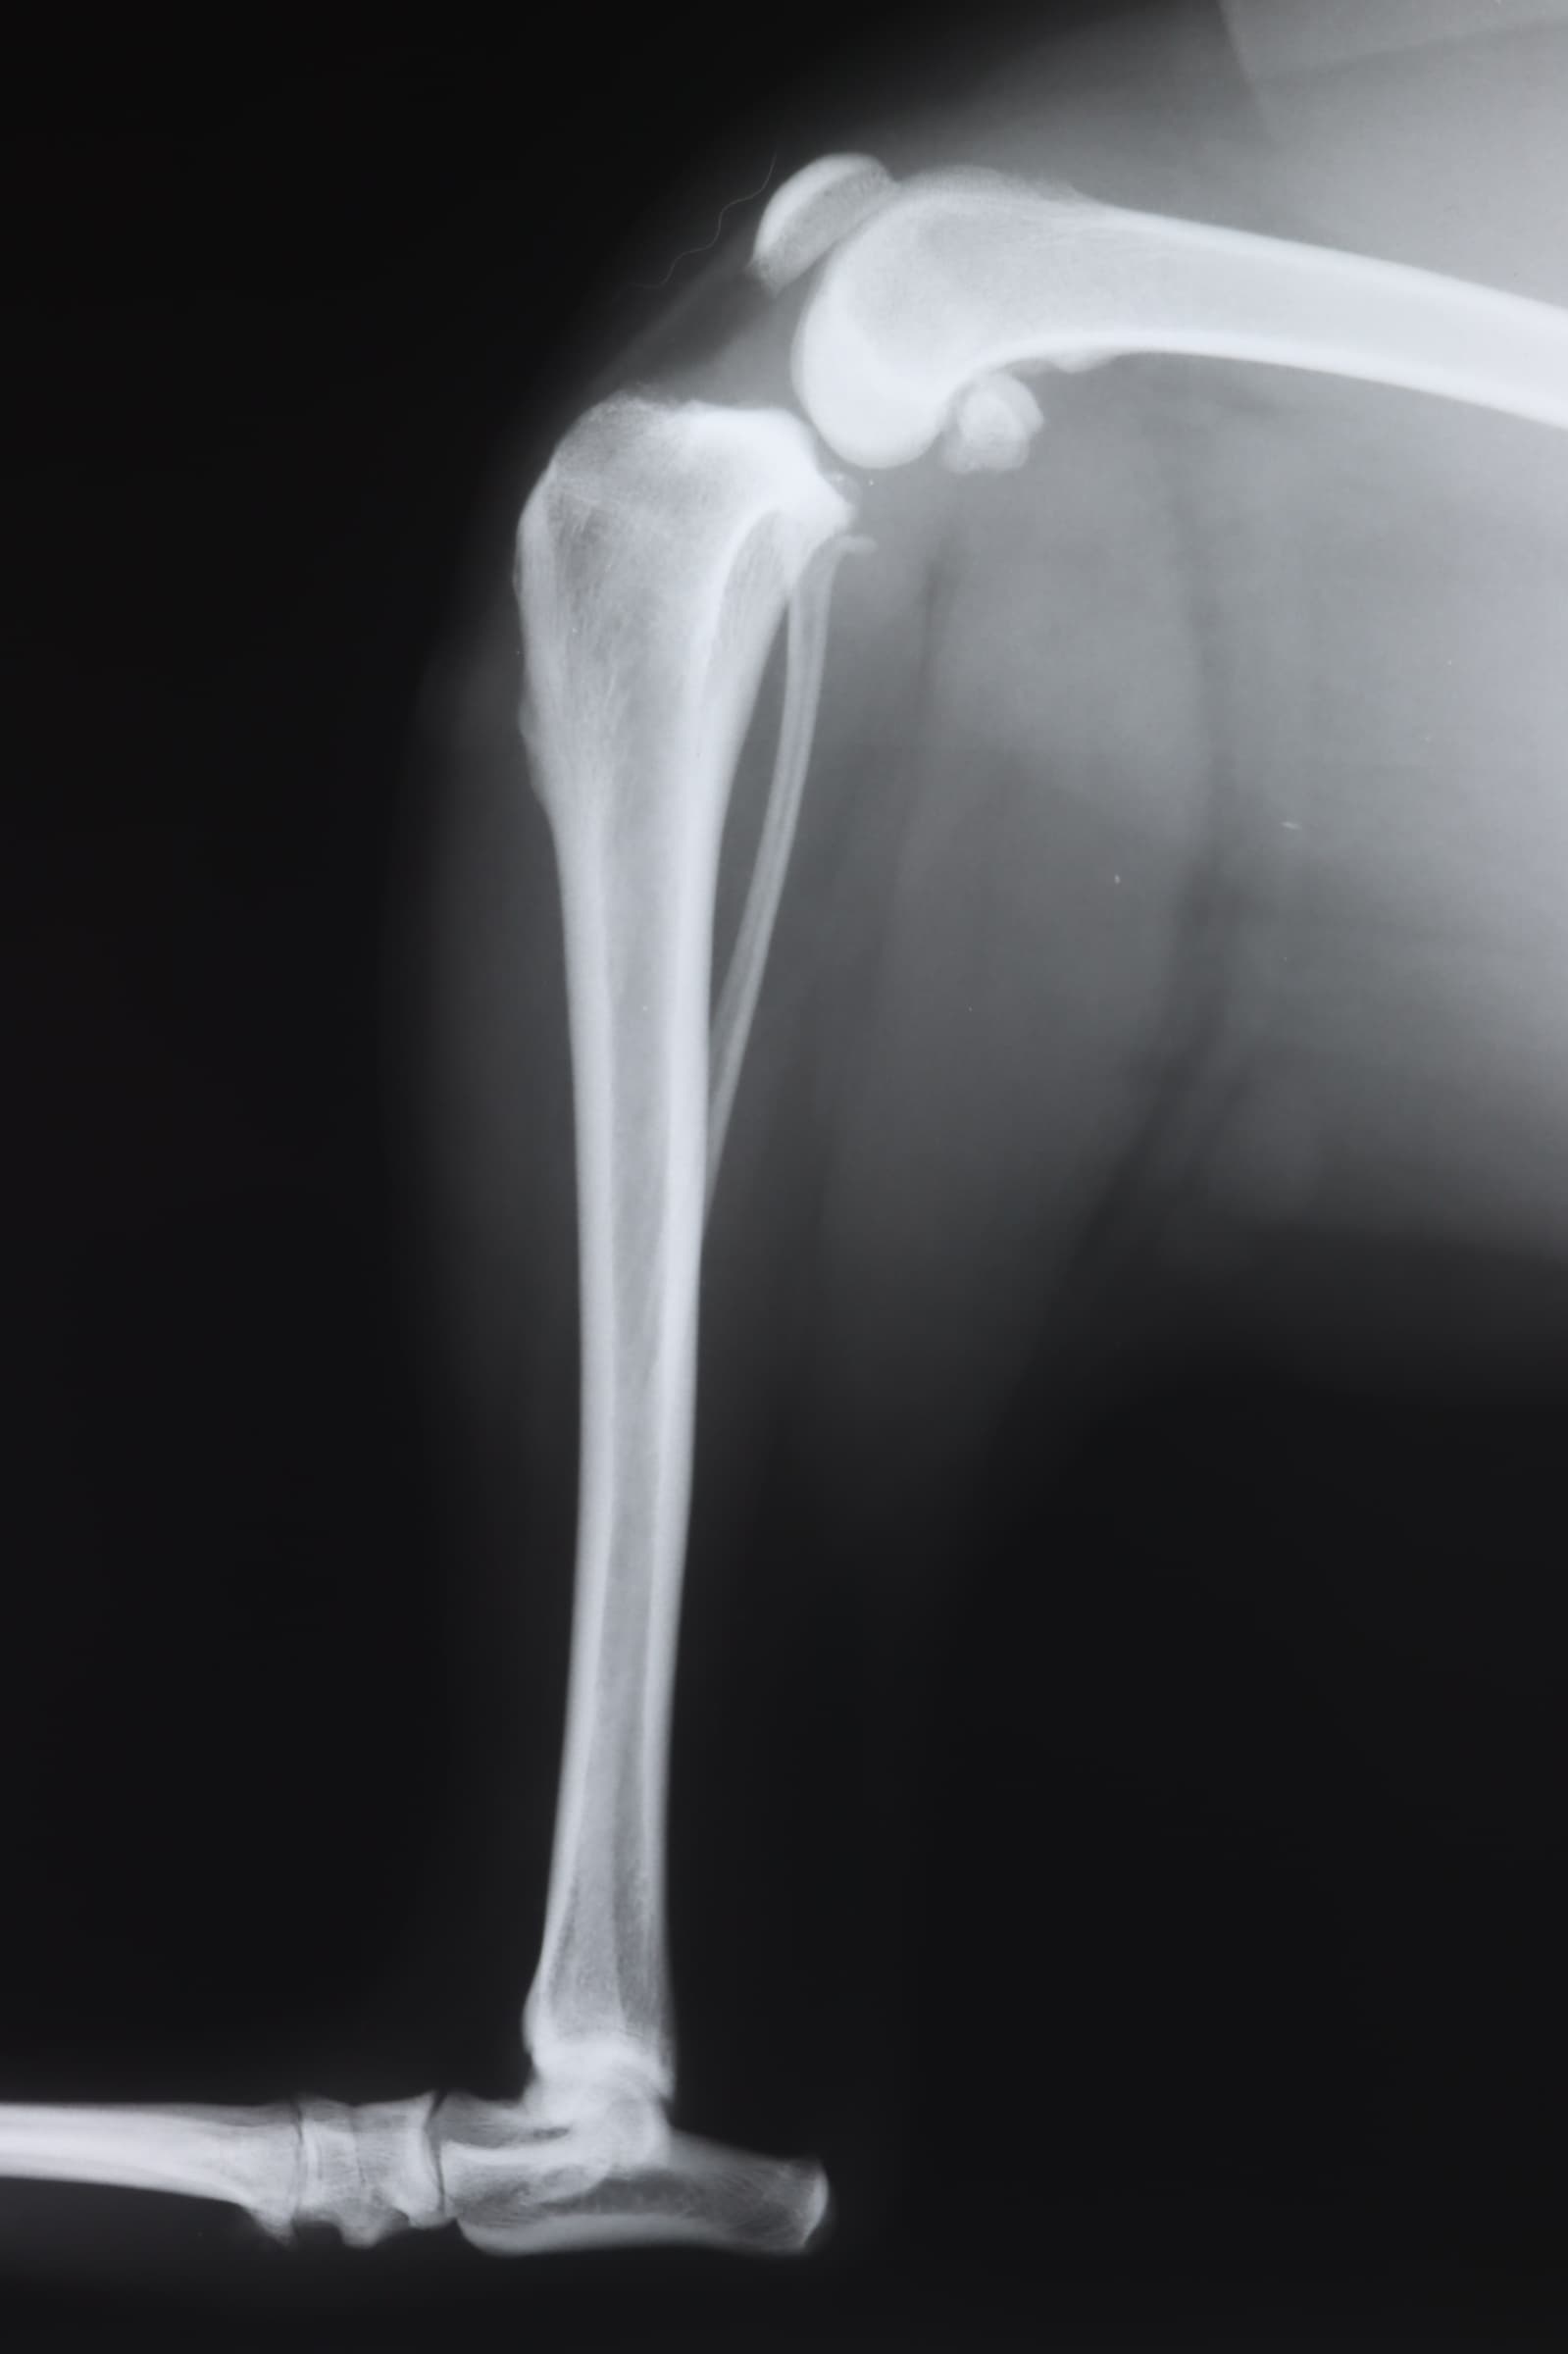

レントゲン写真(後ろ足)

このワンコは15kg超えですが、膝関節の外側に丈夫な糸をかける手術をしました。一般的には15kgを超える場合は、この手術法は成功率が低くなるので、推奨されません。当院では術後ギプスをすることにより、そのような場合も安定化させるとが可能です。40kg近いピットブルが軽快した実績もあります。本来はTPLO手術が適応です。(2024年10月31日)